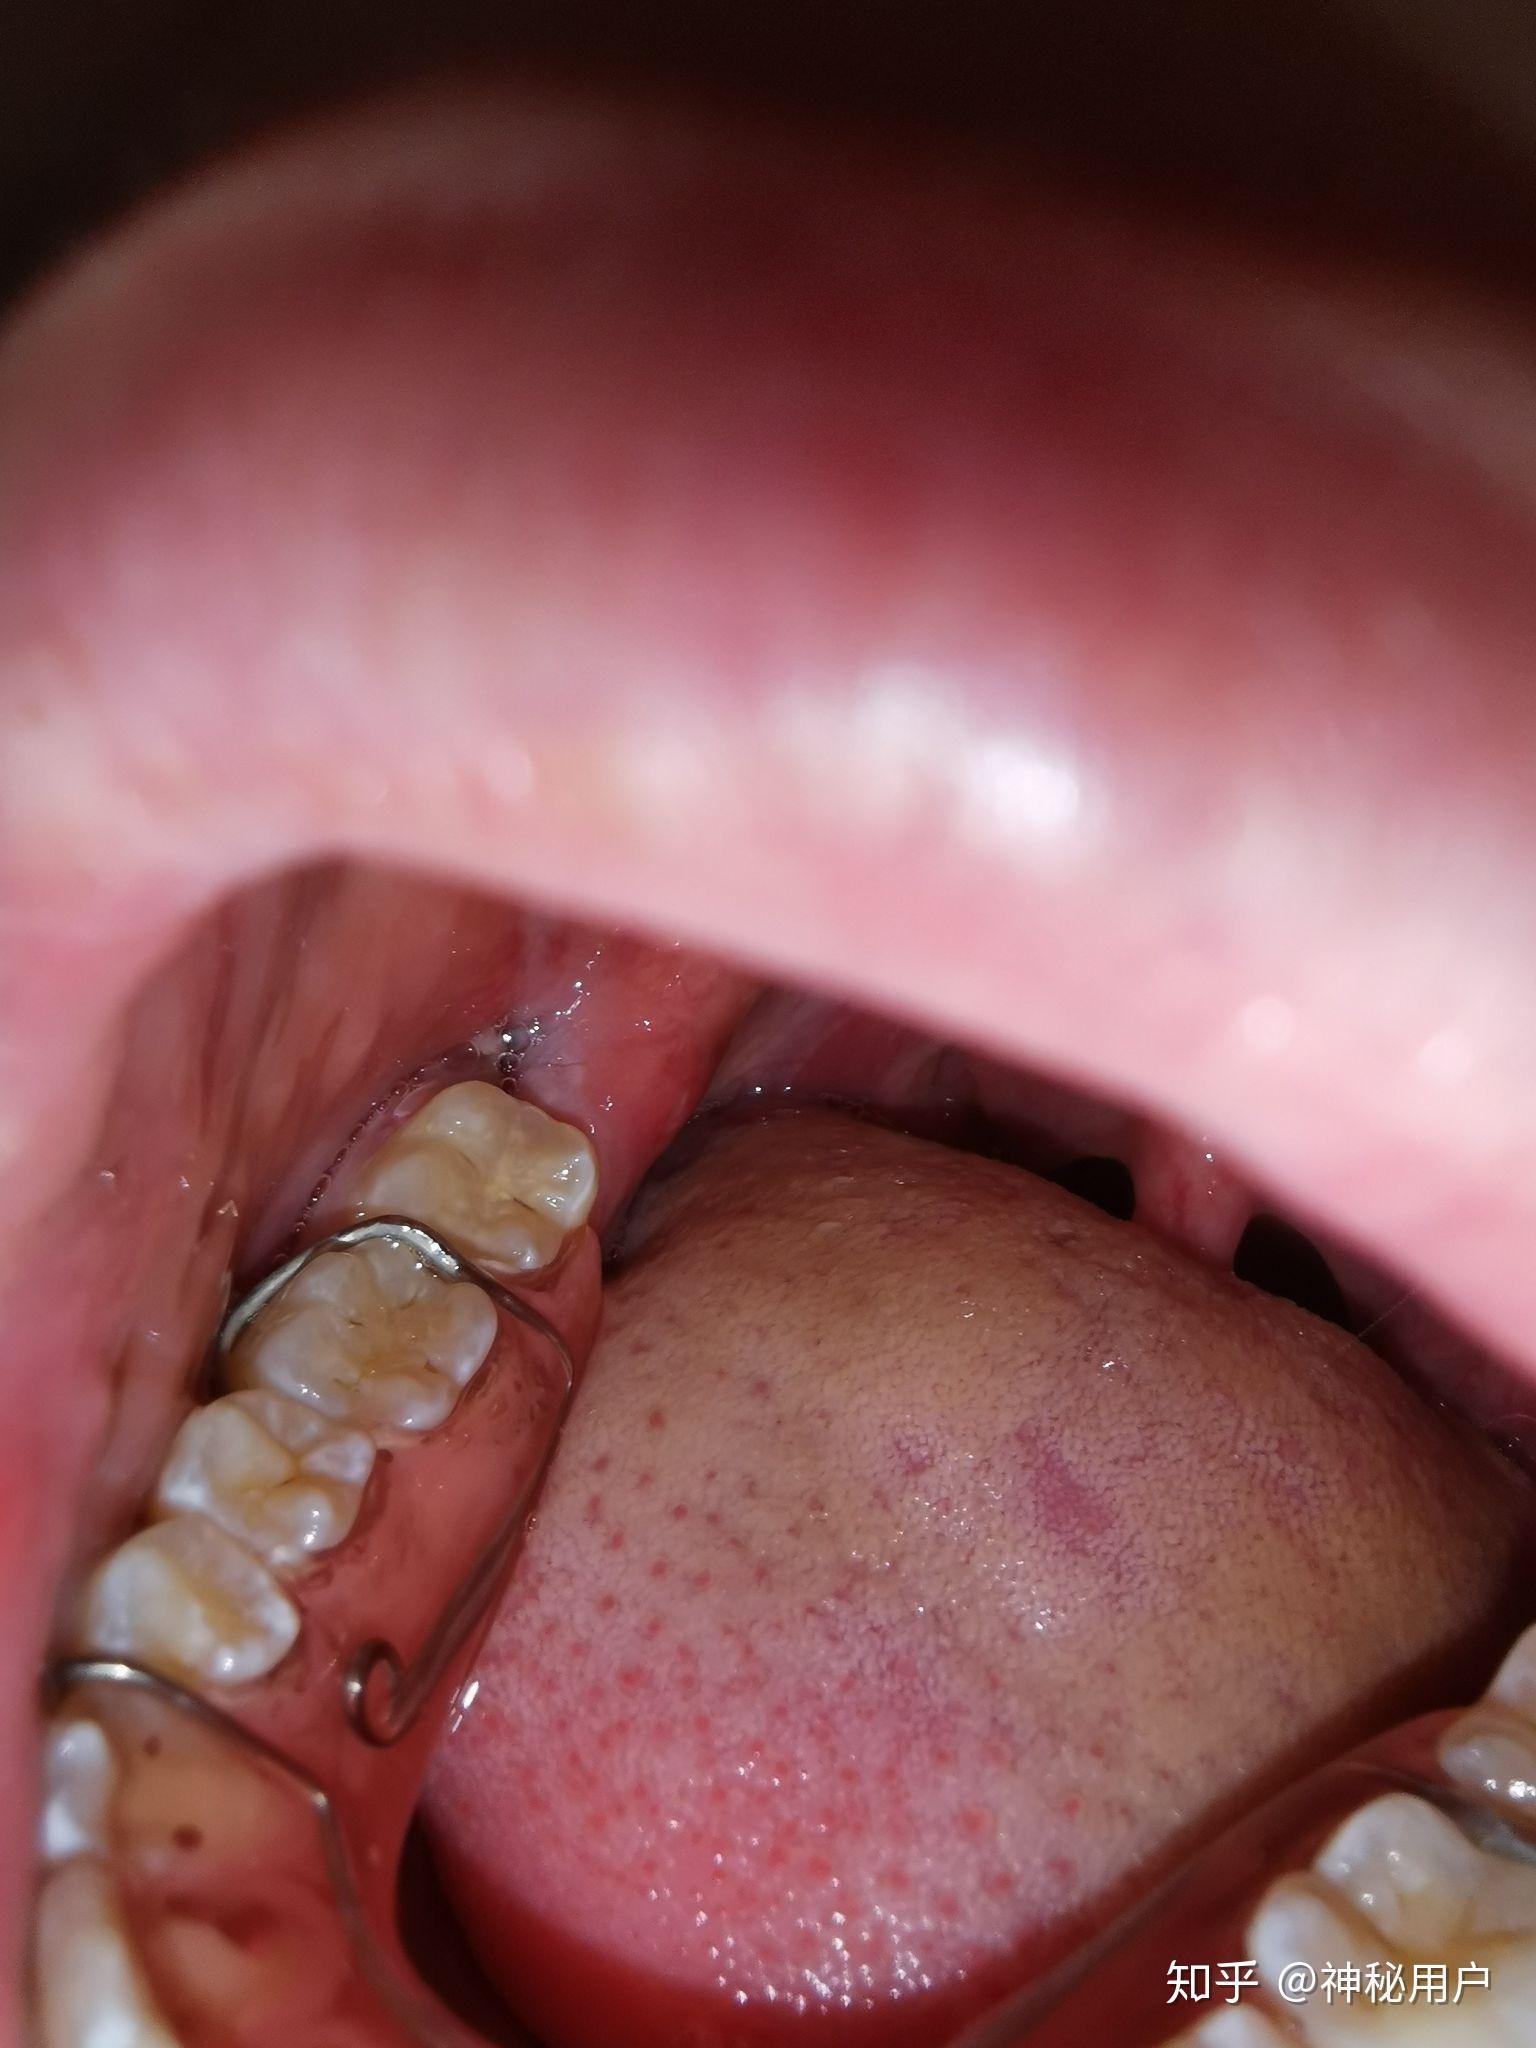

因为矫正拔了这个智齿,将近一个月了,智齿前面的一颗牙后面有个很深的

是食物残渣吗?还是拔牙的时候医生给我安装的什么东西. 患者信息:男